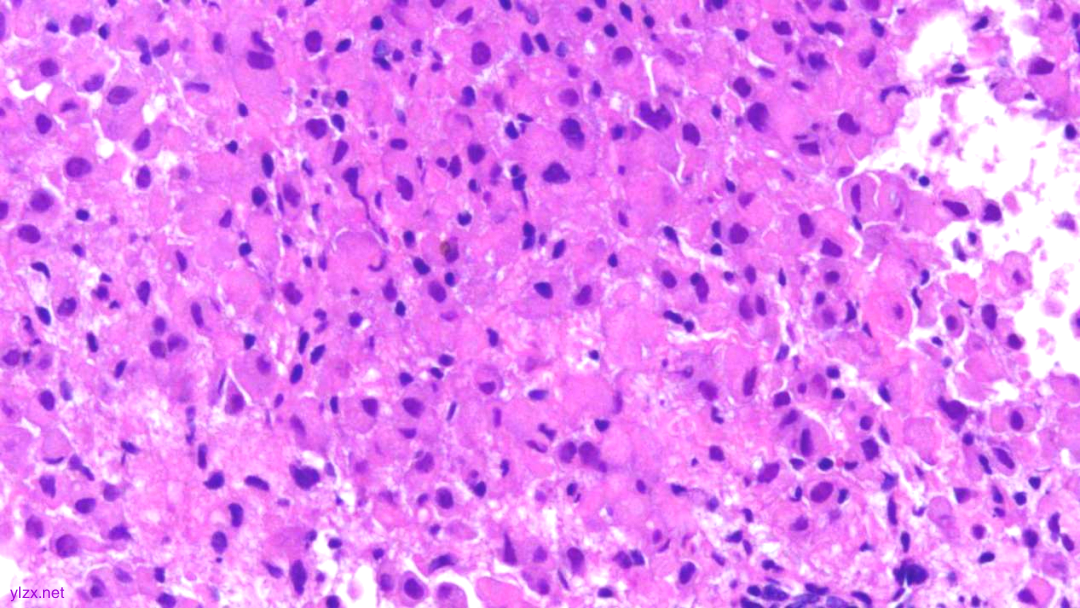

HE:

1.宫颈2点、10点:鳞状上皮下间质内见瘤组织弥漫增生,胞浆宽阔,红染,核小,较一致,部分细胞核偏位,部分细胞可见核仁;

鳞状上皮下间质内见瘤组织弥漫增生,胞浆宽阔、红染,核小,较一致

瘤细胞排列偏稀疏,核小,深染,胞浆红

瘤细胞核偏位,浆红染

高倍瘤细胞见红色核仁